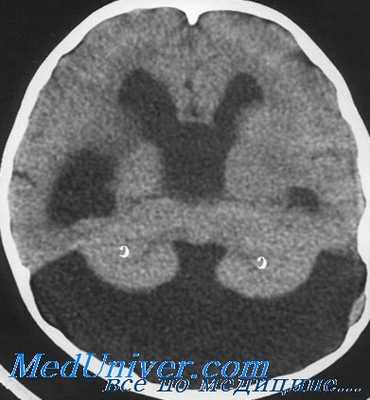

Ведущим методом диагностики хронической дизрезорбтивной гидроцефалии является КТ головного мозга. Патогномоничными признаками хронической дизрезорбтивной гидроцефалии по данным КТ являются:

1. Симметричное расширение желудочковой системы головного мозга с преимущественным баллонообразным расширением передних рогов боковых желудочков, исчезновение «талии» у передних рогов. Степень расширения желудочковой системы определяют путем расчета вентрикулокраниальных индексов (ВКИ) по общепринятой методике.

Вентркуолокраниальный индекс (ВКИ) З определяется как отношение максимальной ширины III желудочка к наибольшему расстоянию между внутренними пластинками костей черепа. Предел нормы для ВКИЗ у людей моложе 30 лет составляет 2,7%; от 31 до 40 лет - 2,9%; от 41 до 60 лет - 3,3%; от 61 до 70 лет — 3,9%; старше 70 лет — 4,3%. ВКИ4 получают путем расчета отношения ширины IV желудочка к максимальному диаметру задней черепной ямки, а ВКИ тел — как отношение расстояния наиболее удаленных точек тел боковых желудочков к максимальному расстоянию между внутренними пластинками костей черепа. ВКИ4 является наиболее постоянным для всех возрастных групп, его верхняя граница нормы составляет 13%.

2. Появление перивентрикулярного снижения плотности мозгового вещества — перивентрикулярного лейкоареоза (ПЛ). В распространенности ПЛ выделяют 3 стадии. На первой стадии, соответствующей появлению первых симптомов заболевания, очаги ПЛ локализуются только вокруг верхушек передних рогов боковых желудочков наподобие «кисточек на ушах рыси». Во вторую стадию очаги ПЛ располагаются вокруг передних, задних и нижних рогов боковых желудочков.

И наконец, на более поздней, третьей стадии, которая соответствует далеко зашедшим случаям дизрезорбтивной гидроцефалии, обширные очаги ПЛ прилегают ко всем участкам желудочковой системы (передние рога, тела, задние и нижние рога боковых желудочков, перивентрикулярная область III и IV желудочков).

3. Сужение и отсутствие визуализации субарахноидальных щелей головного мозга.